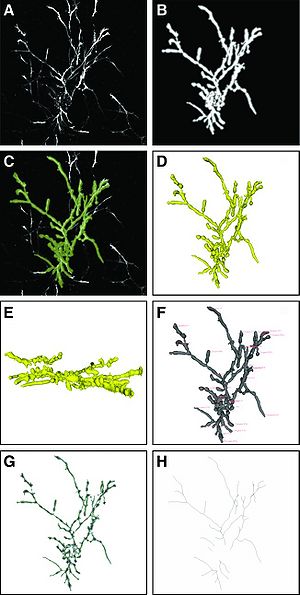

- 9.32 Spiny Versus Stubby: 3D Reconstruction of Human Myenteric (type I) Neurons